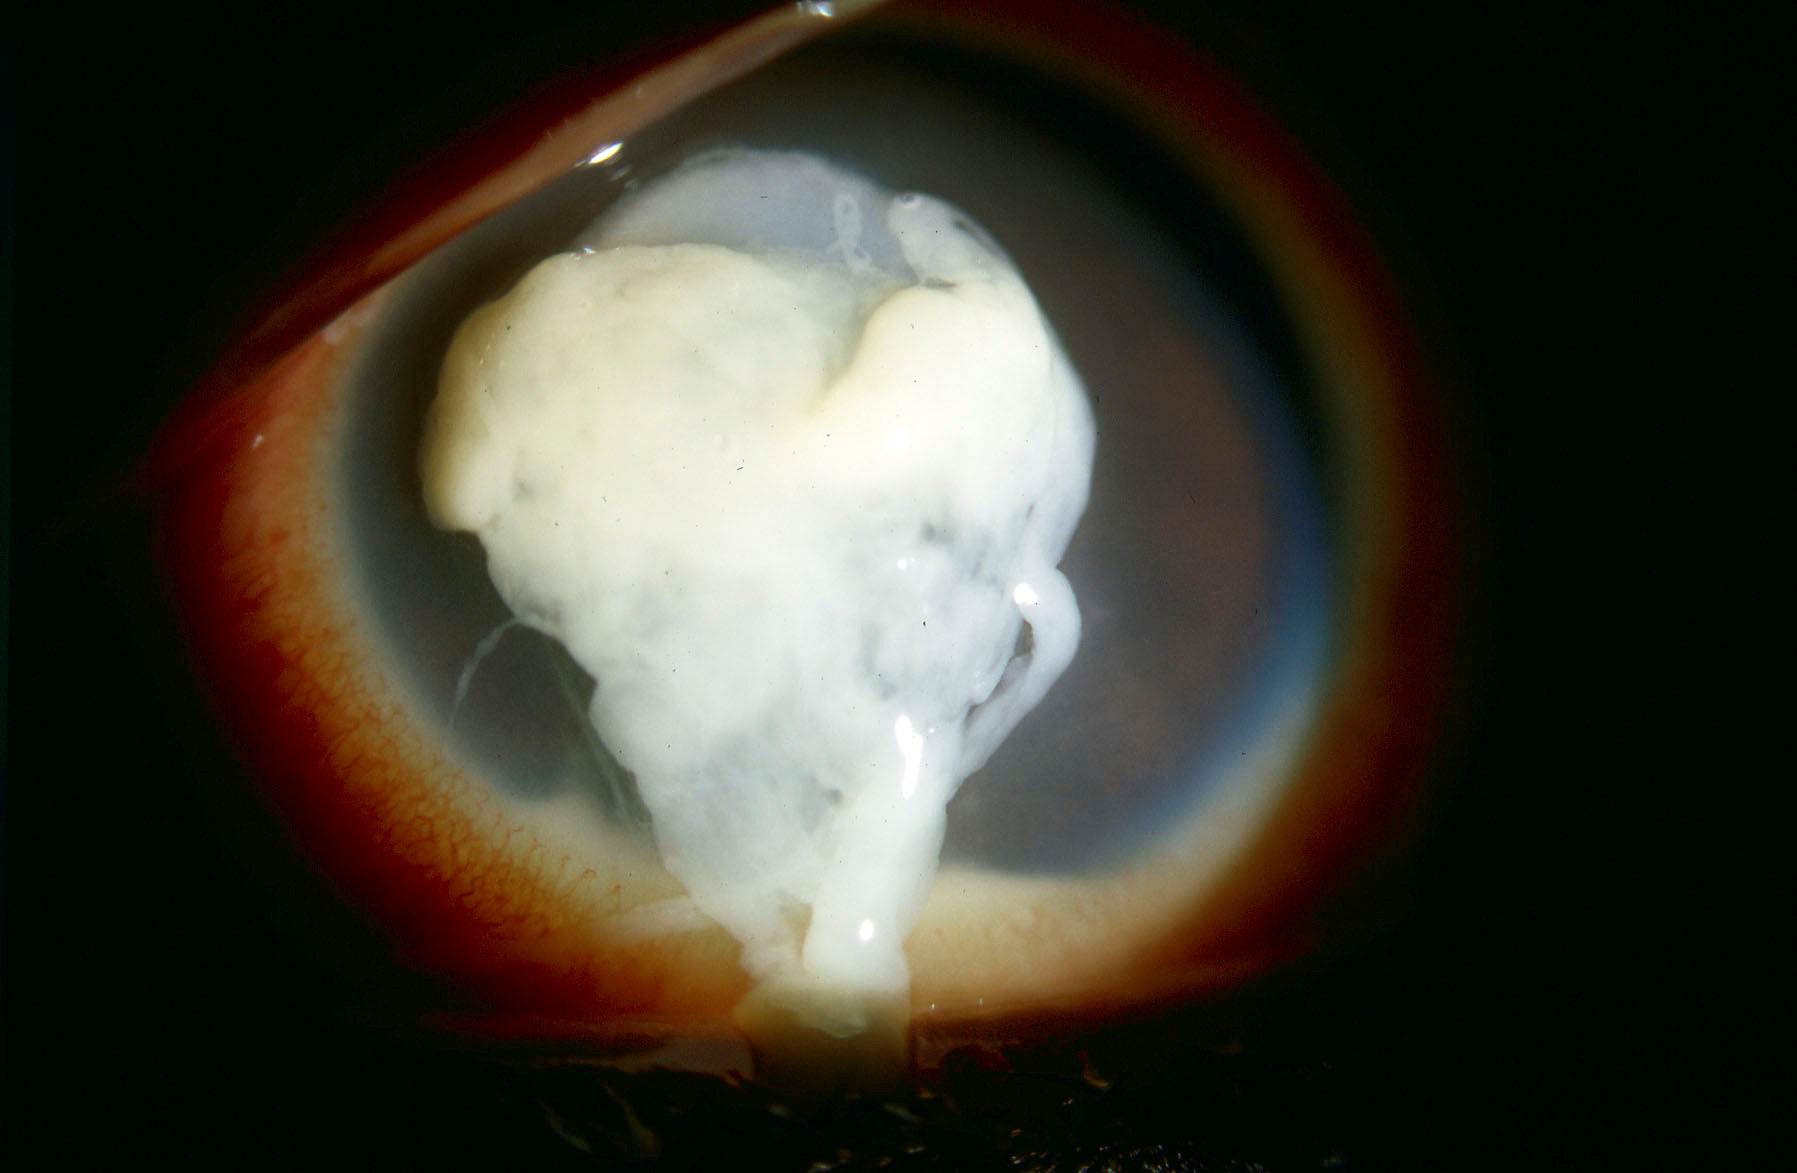

Ill-fitting lenses can cause eye pain, bacterial infections, and corneal ulcers. One study found that wearing decorative lenses increased the risk for developing keratitis, a potentially blinding infection that causes an ulcer in the eye. This increased risk was over 16 times more likely than those seen in vision correcting (“regular”) lenses.

“I’ve seen many young patients who were not aware of the dangers of these products and are now living with permanent vision loss,” said Thomas L. Steinemann, MD, Professor of Ophthalmology at Case Western Reserve University/MetroHealth Medical Center and a Prevent Blindness volunteer. “Even if the lenses are cosmetic or non-correcting, they are still classified as medical devices and should only be prescribed by an eye care professional.”

Images of serious eye injuries caused by illegally sold lenses (photo 1 and photo 2, courtesy of Dr. Thomas L. Steinemann) and an image of an unauthorized cosmetic contact lens display (photo 3, courtesy of the FDA) are available on the Ohio Attorney General's website.